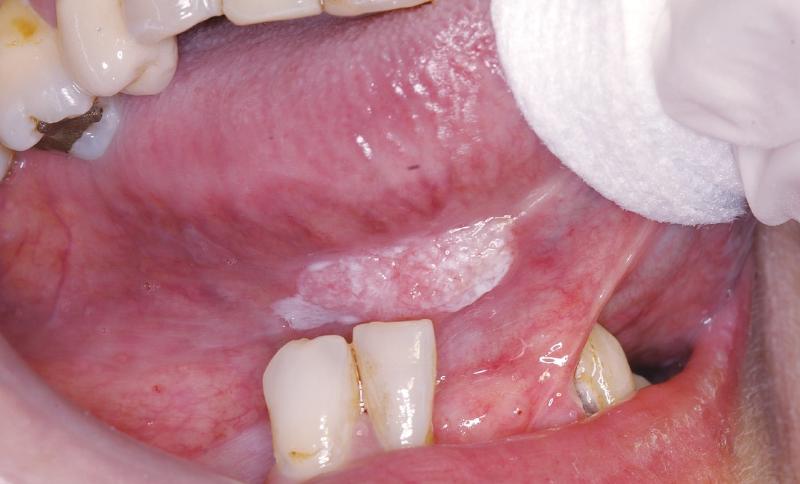

CASO CLÍNICO LXIII

Diagnóstico anatomopatológico e inmunopatológico